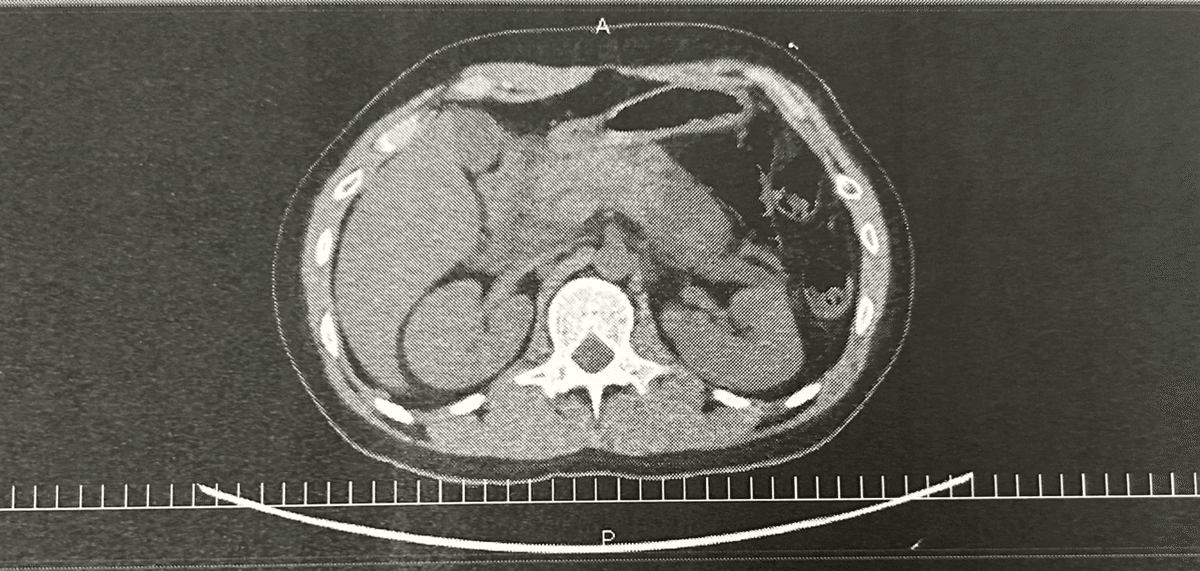

そして、抗がん剤治療をを始めて2ヶ月後の2023年7月に抗がん剤の副作用で急性膵炎を引き起こしました。急性膵炎とは膵臓が炎症を起こし膵臓が分泌する膵液がお腹の中に漏れ出す病気です。膵液は本来、お肉などのタンパク質を溶かす働きを持っているのですが、人間の体もほとんどがタンパク質なのでまるでお腹の中を溶かされているような痛みが6時間ほど続きました。よく出産と同程度の痛みと言われています。このときは本当に痛くて病室でずっと叫んでいました。間違いなく人生で1番の痛みです。

その後は1週間の絶飲食を経て、症状が回復しましたが、問題なのはこの急性膵炎を引き起こした抗がん剤が使えなくなるという点です。抗がん剤にも様々な種類があり、私の病気にはこの抗がん剤以外だと治る見込みがなかったのです。